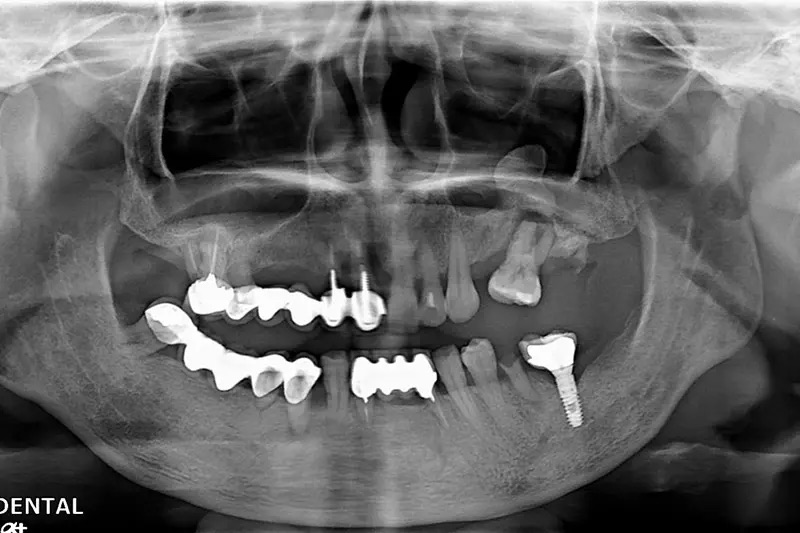

植牙成功案例